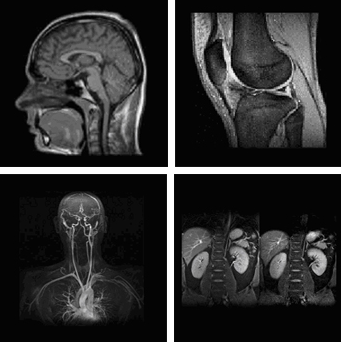

Voorbeelden van MRI afbeeldingen

MRI is een techniek om afbeeldingen van het lichaam te maken zonder dat gebruik wordt gemaakt van röntgenstralen. Met de MRI-apparatuur worden doorsnede foto's van uw lichaam gemaakt waarbij gebruik wordt gemaakt van een sterk magnetisch veld en radiogolven.